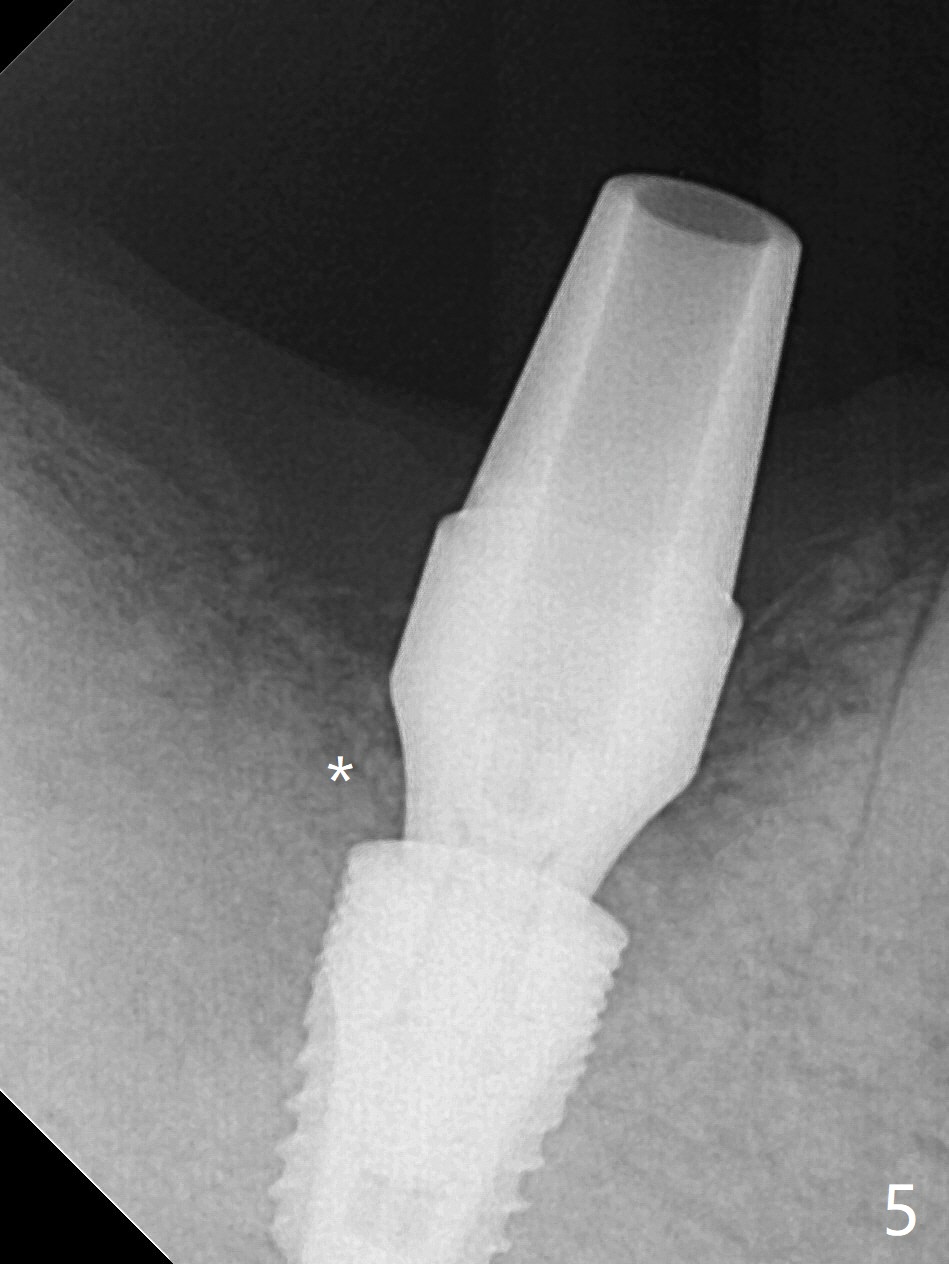

After extraction of the tooth #30, hemorrhage is excessive. With incision and buccal flap elevation, it is easy to remove residual granulation tissue and see the bony defect. With gauze pressure, hemostasis is manageable. Osteotomy is established in the mesial socket, i.e., mesial slope (Fig.1 yellow dashed line) with 2 mm initial drill from DIO Sinus Master Kit with 6 mm stop. After use of 3.8 and 3.6 mm round burs from the Master Kit for 6 mm, 4.1-5x8 mm drills from SM Kit are used with 50 RPM to control depth until the patient feels light pain with infiltration anesthesia. A 5.3 mm tap drill is inserted with 50 Ncm (Fig.2). A 5.3x8 mm SM implant is placed with >55 Ncm with clearance from the Inferior Alveolar Canal (Fig.3 red dashed line) with tightening a 5.8x7(6) mm abutment. The implant is subcrestal mesiolingually, equicrestal buccally and supracrestal distally (Fig.3 thread exposure distally between arrows). With Osteogen plug placed in the distal socket, allograft is placed around the implant and abutment (Fig.4 *). Periodontal dressing is applied following buccal placement of Collagen Dressing and suturing. The gingiva around the abutment is healthy 3.5 months postop; new bone appears to form distocoronal to the implant (Fig.5,6 *).